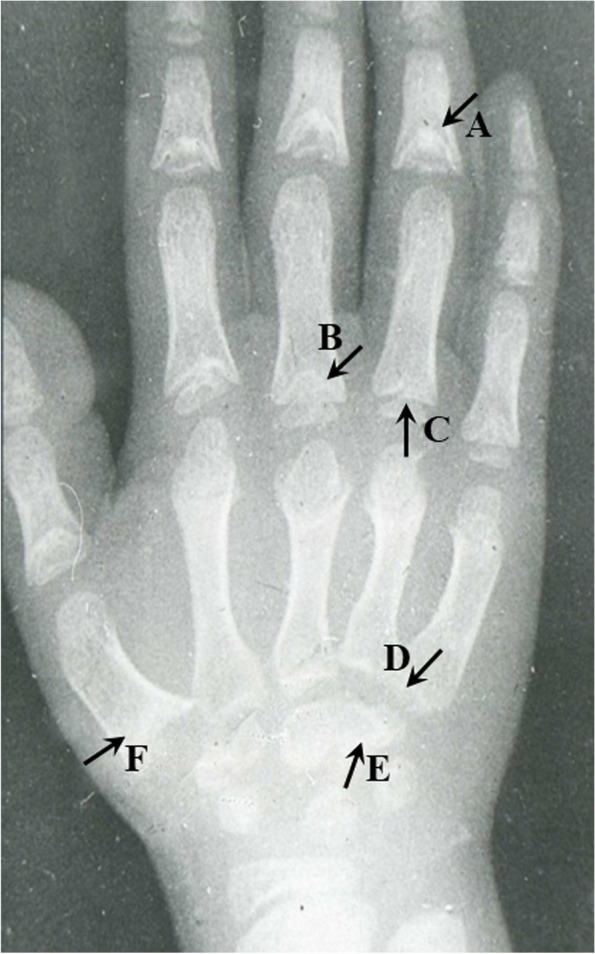

Anteroposterior radiographs of the right hand of each subject were taken to observe the pathological alterations of metaphysis, distal end of phalanges, epiphysis, and carpals. Well-trained and experienced radiologists took the radiographs and followed the standard operating procedures strictly. X-ray pathological changes were extracted by two experienced orthopedic surgeons. The diagnostic criteria of X-ray radiographs for KBD are shown in Supplementary data 1, and an example of pathological X-ray radiograph changes of KBD is shown in Fig. 1. In addition, clinical symptoms were also checked by orthopedic surgeons. The examination checklist and evaluation standard were shown in Supplementary data 2. Finally, 26 features were extracted according to the evaluation standard (as lay-out in Table 1). KBD was diagnosed by three experienced experts according to X-ray pathological changes, clinical manifestations following the national diagnostic criteria (WS/T207-2010).

Fig. 1.

Examples of X-ray pathological changes of an eight-year old KBD boy. A A large defect with cone shaped showed in metaphysis alterations. There is an early closure of epiphysis line; B A large defect in metaphysis; C Cone shaped epiphysis; D Sclerosis in bottom of metacarpal bone; E Irregular marginal with sclerosis in carpal; F A large defect with sclerosis in carpal